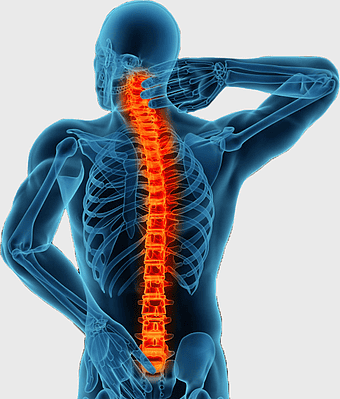

neck pain treatment, back pain relief, cervical spine anatomy, physical therapy exercises, spine health, musculoskeletal pain, medical imaging analysis -

vertebral column, spinal fusion, minimally invasive spine surgery, back pain, human anatomy, medical illustration, skeletal health -

spine skeleton illustration, orthopedic surgery, musculoskeletal disorder, human body anatomy, skeletal health, medical imaging, spine health analysis -

neck pain treatment, cervical spine discomfort, chiropractic care backbone, back pain relief methods, vertebral health solutions, spinal alignment therapy, musculoskeletal wellness tips -